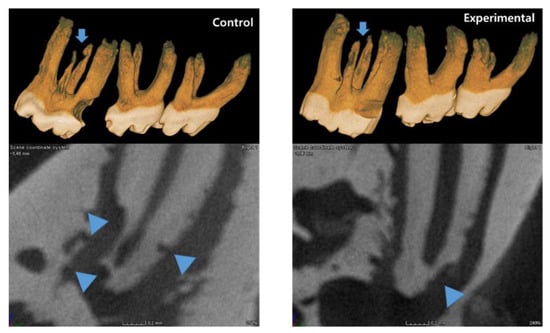

3.1. The Application of 4HR Inhibited Root Resorption during OTM